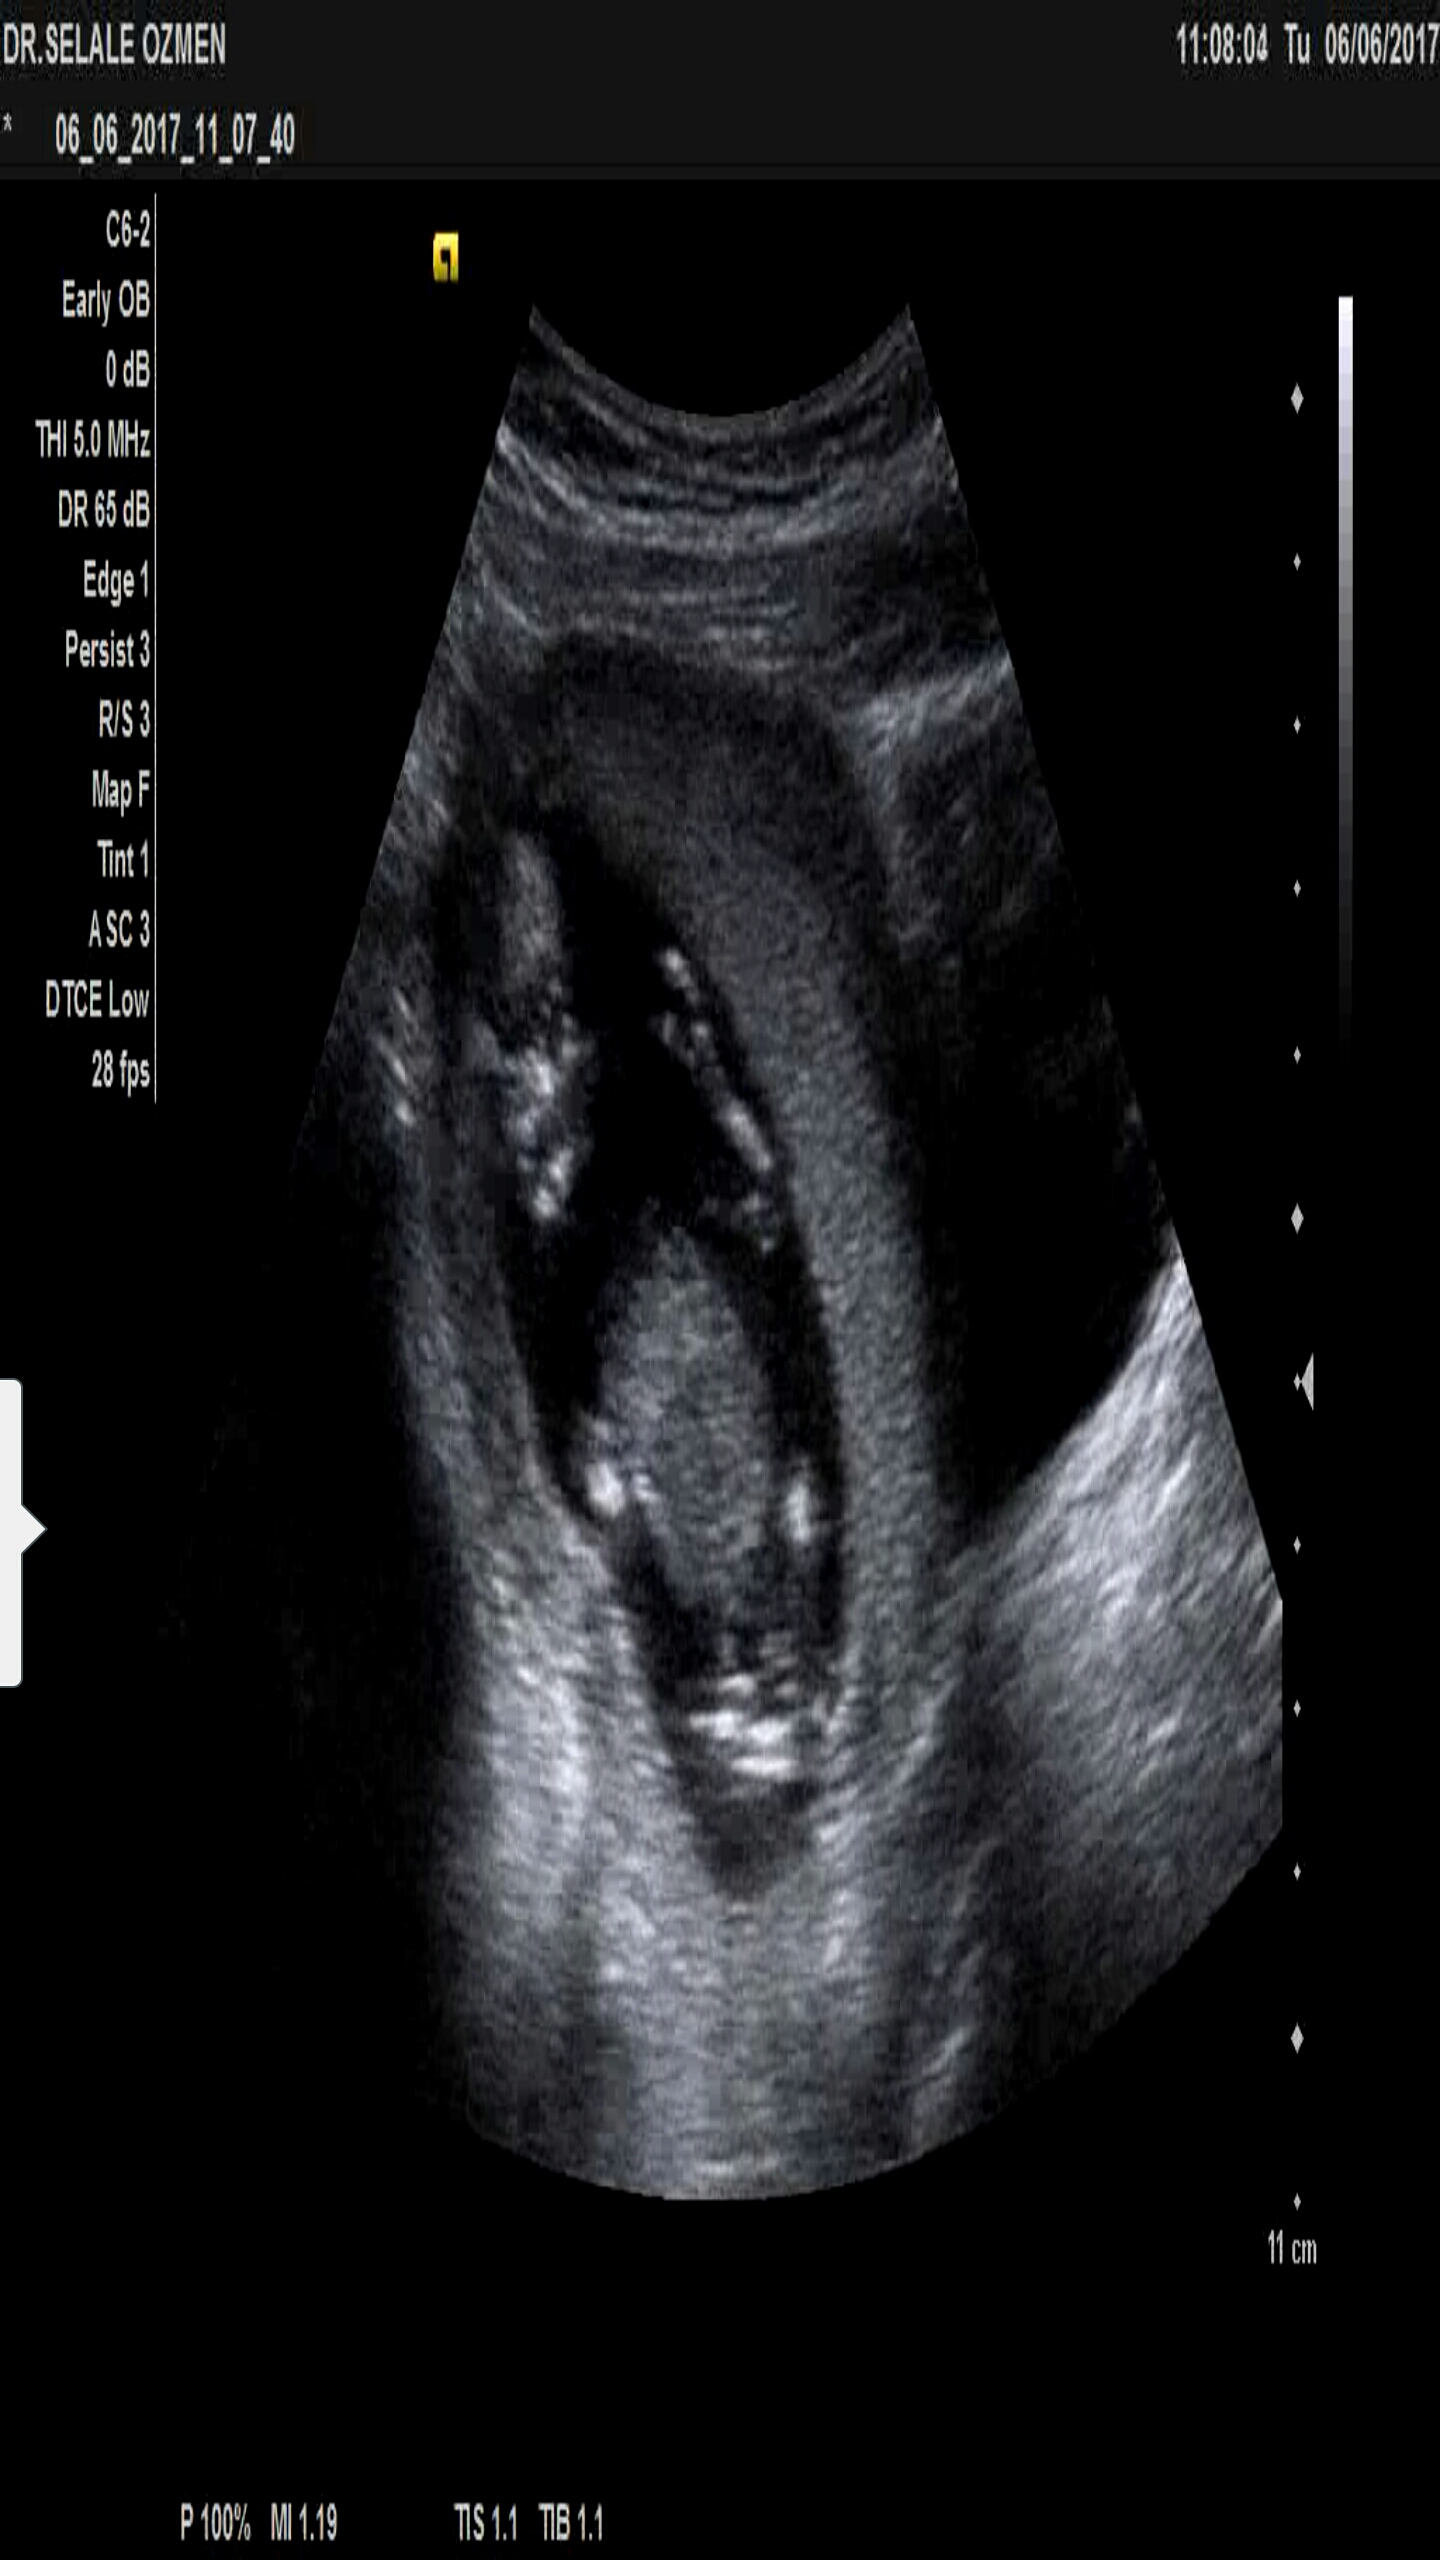

Merhaba bende tahmin alabilir miyim acaba🙂 ilk fotoda 10 haftalik ikincisinde 13 haftalik 🙂

Screenshot_2017-06-22-14-51-10.jpg